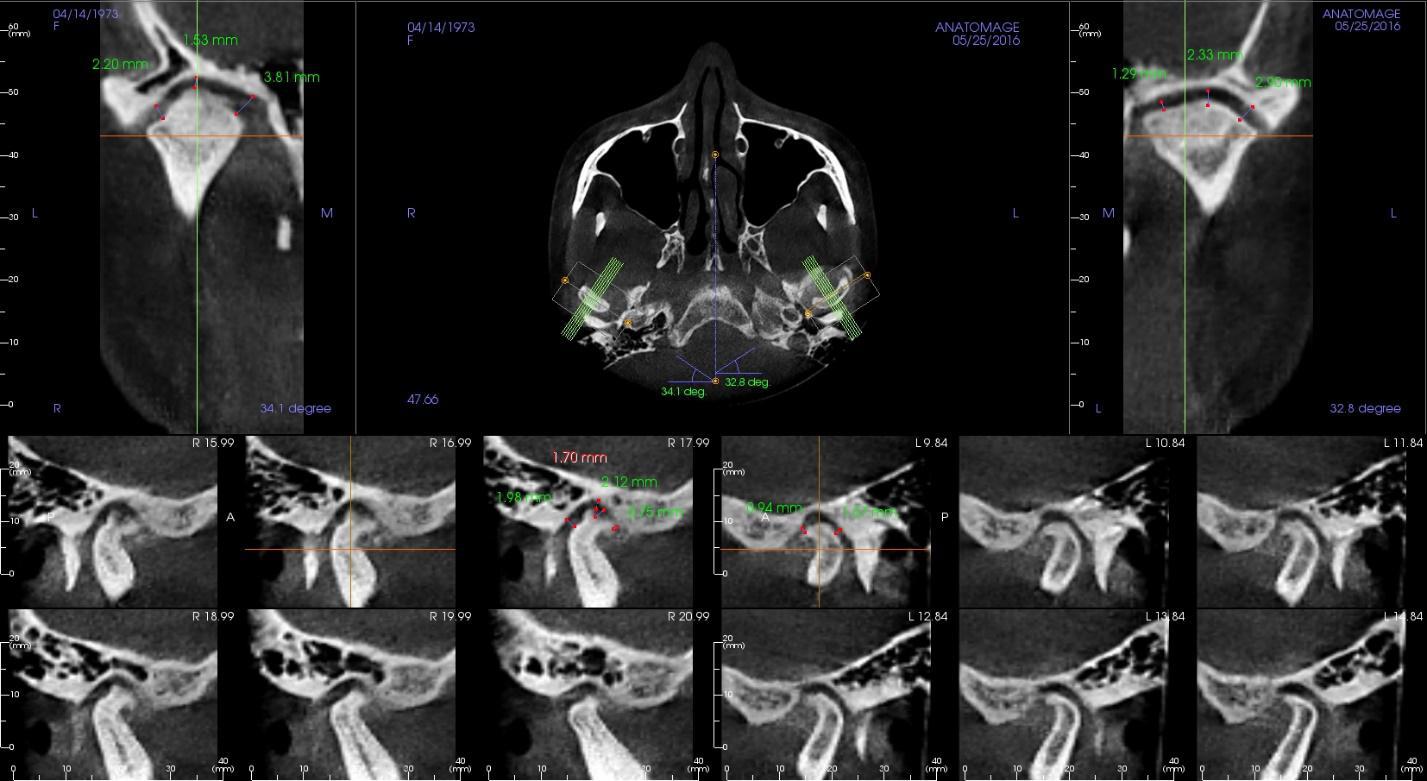

Основана на компьютерной томографии; цифровом паспорте пациента -3D Цефалометрии;

Полный расчет исходной ситуации в 3D цефалометрии. Составление плана лечения (ортосетап) в программе 3D Shape Ortodont.Загрузка КТ пациента-учет «движения корней» при лечении. Единственно правильный перенос положения брекетов или элайнеров - 3D печать полученного в программе результата (примеры представлены ниже на фото).

Индивидуальные параметры пациента: углы, плоскости, пути, положения элементов ВНЧС не только фиксируются ,но и самое главное переносятся в цифровом формате во фрезерный центр собственной лаборатории клиники.